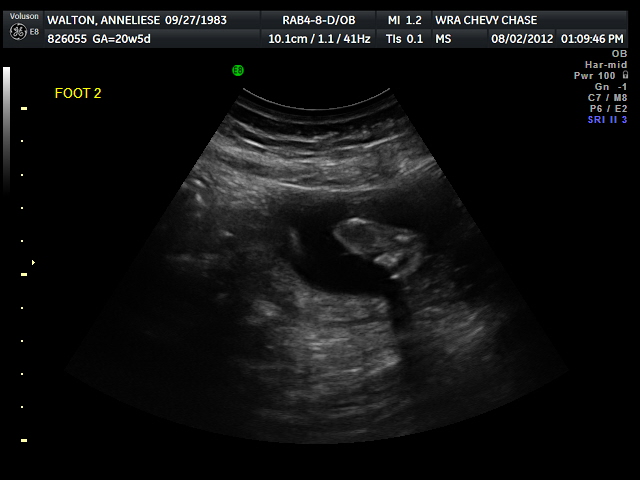

IT'S (SHE'S) A GIRL!!!

Last week we finally found out the gender of our child. It's a girl! wooooot! We are excited, Liese is already working on a girly baby blanket.

This is the evidence, I'm convinced.

We'll have better pictures towards the end of December.

She kept licking the wall of the placenta, we're going to have one of those weird kids that licks everything....